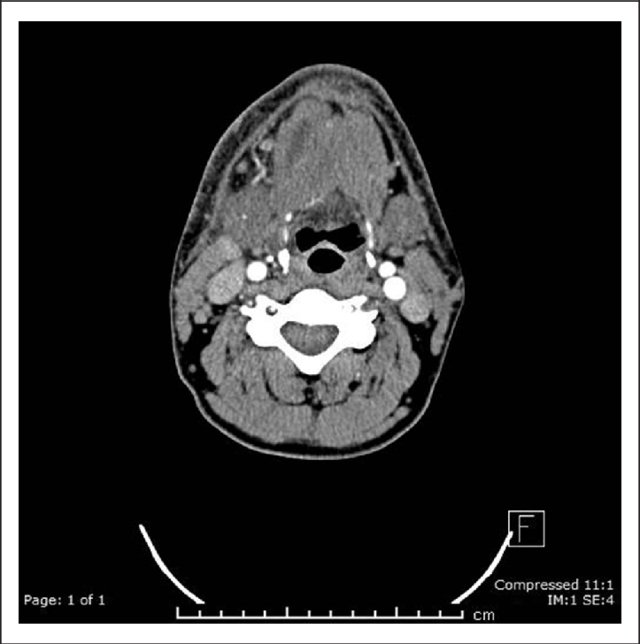

Abscess of the Anterior Belly of the Digastric

https://pubmed.ncbi.nlm.nih.gov/31232606/

Abscesses within muscles in the Head and Neck are exceptionally rare, others having been described by Luc, Bezold, and Citelli. Mr Pankhania describes the first ever case of this variety under the tongue in the anterior digastric muscle.